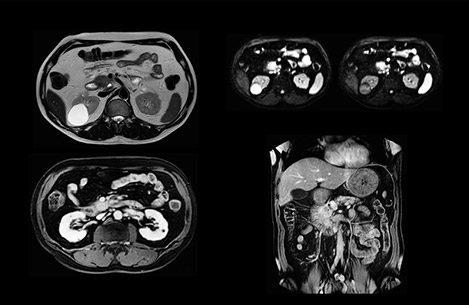

Comparison of liver MRI with and without MultiVane XD motion correction

In this example the image quality of the MultiVane XD images is evidently better than in the images without MultiVane XD. Ingenia 1.5T with dS Torso coil solution.